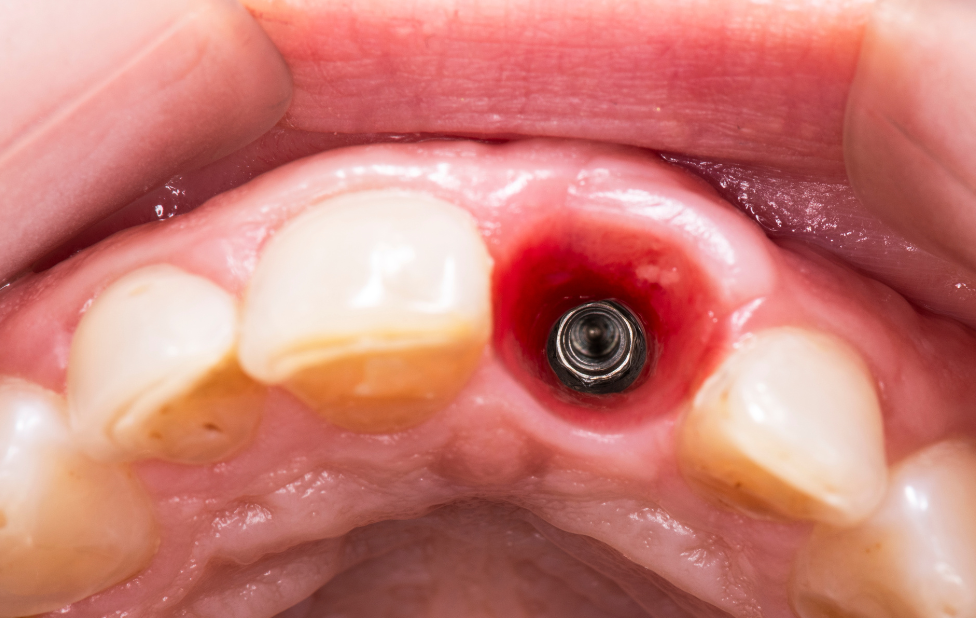

Les infections péri-implantaires comptent parmi les complications les plus courantes en implantologie dentaire. Lorsqu’elles ne sont pas détectées rapidement, elles peuvent entraîner une inflammation sévère, une perte osseuse et compromettre la stabilité à long terme des

La réussite d’un implant dentaire repose sur un concept fondamental : l’ostéointégration. Il s’agit de la fusion naturelle entre l’implant et l’os de la mâchoire, garantissant à la fois la stabilité et la durabilité du traitement. À Casablanca, les cliniques spécialisées mettent un accent particulier sur la qualité de l’os et la planification chirurgicale pour assurer le succès de chaque intervention.

Après la pose d’un implant dentaire, la réussite du traitement ne dépend pas uniquement de la chirurgie, mais également des soins et de l’entretien quotidien. Un implant bien entretenu peut durer plusieurs décennies, offrant confort, fonctionnalité et esthétique. À Casablanca, les cliniques spécialisées en implantologie dentaire mettent l’accent sur un suivi rigoureux et des conseils pratiques pour garantir la longévité de votre implant.